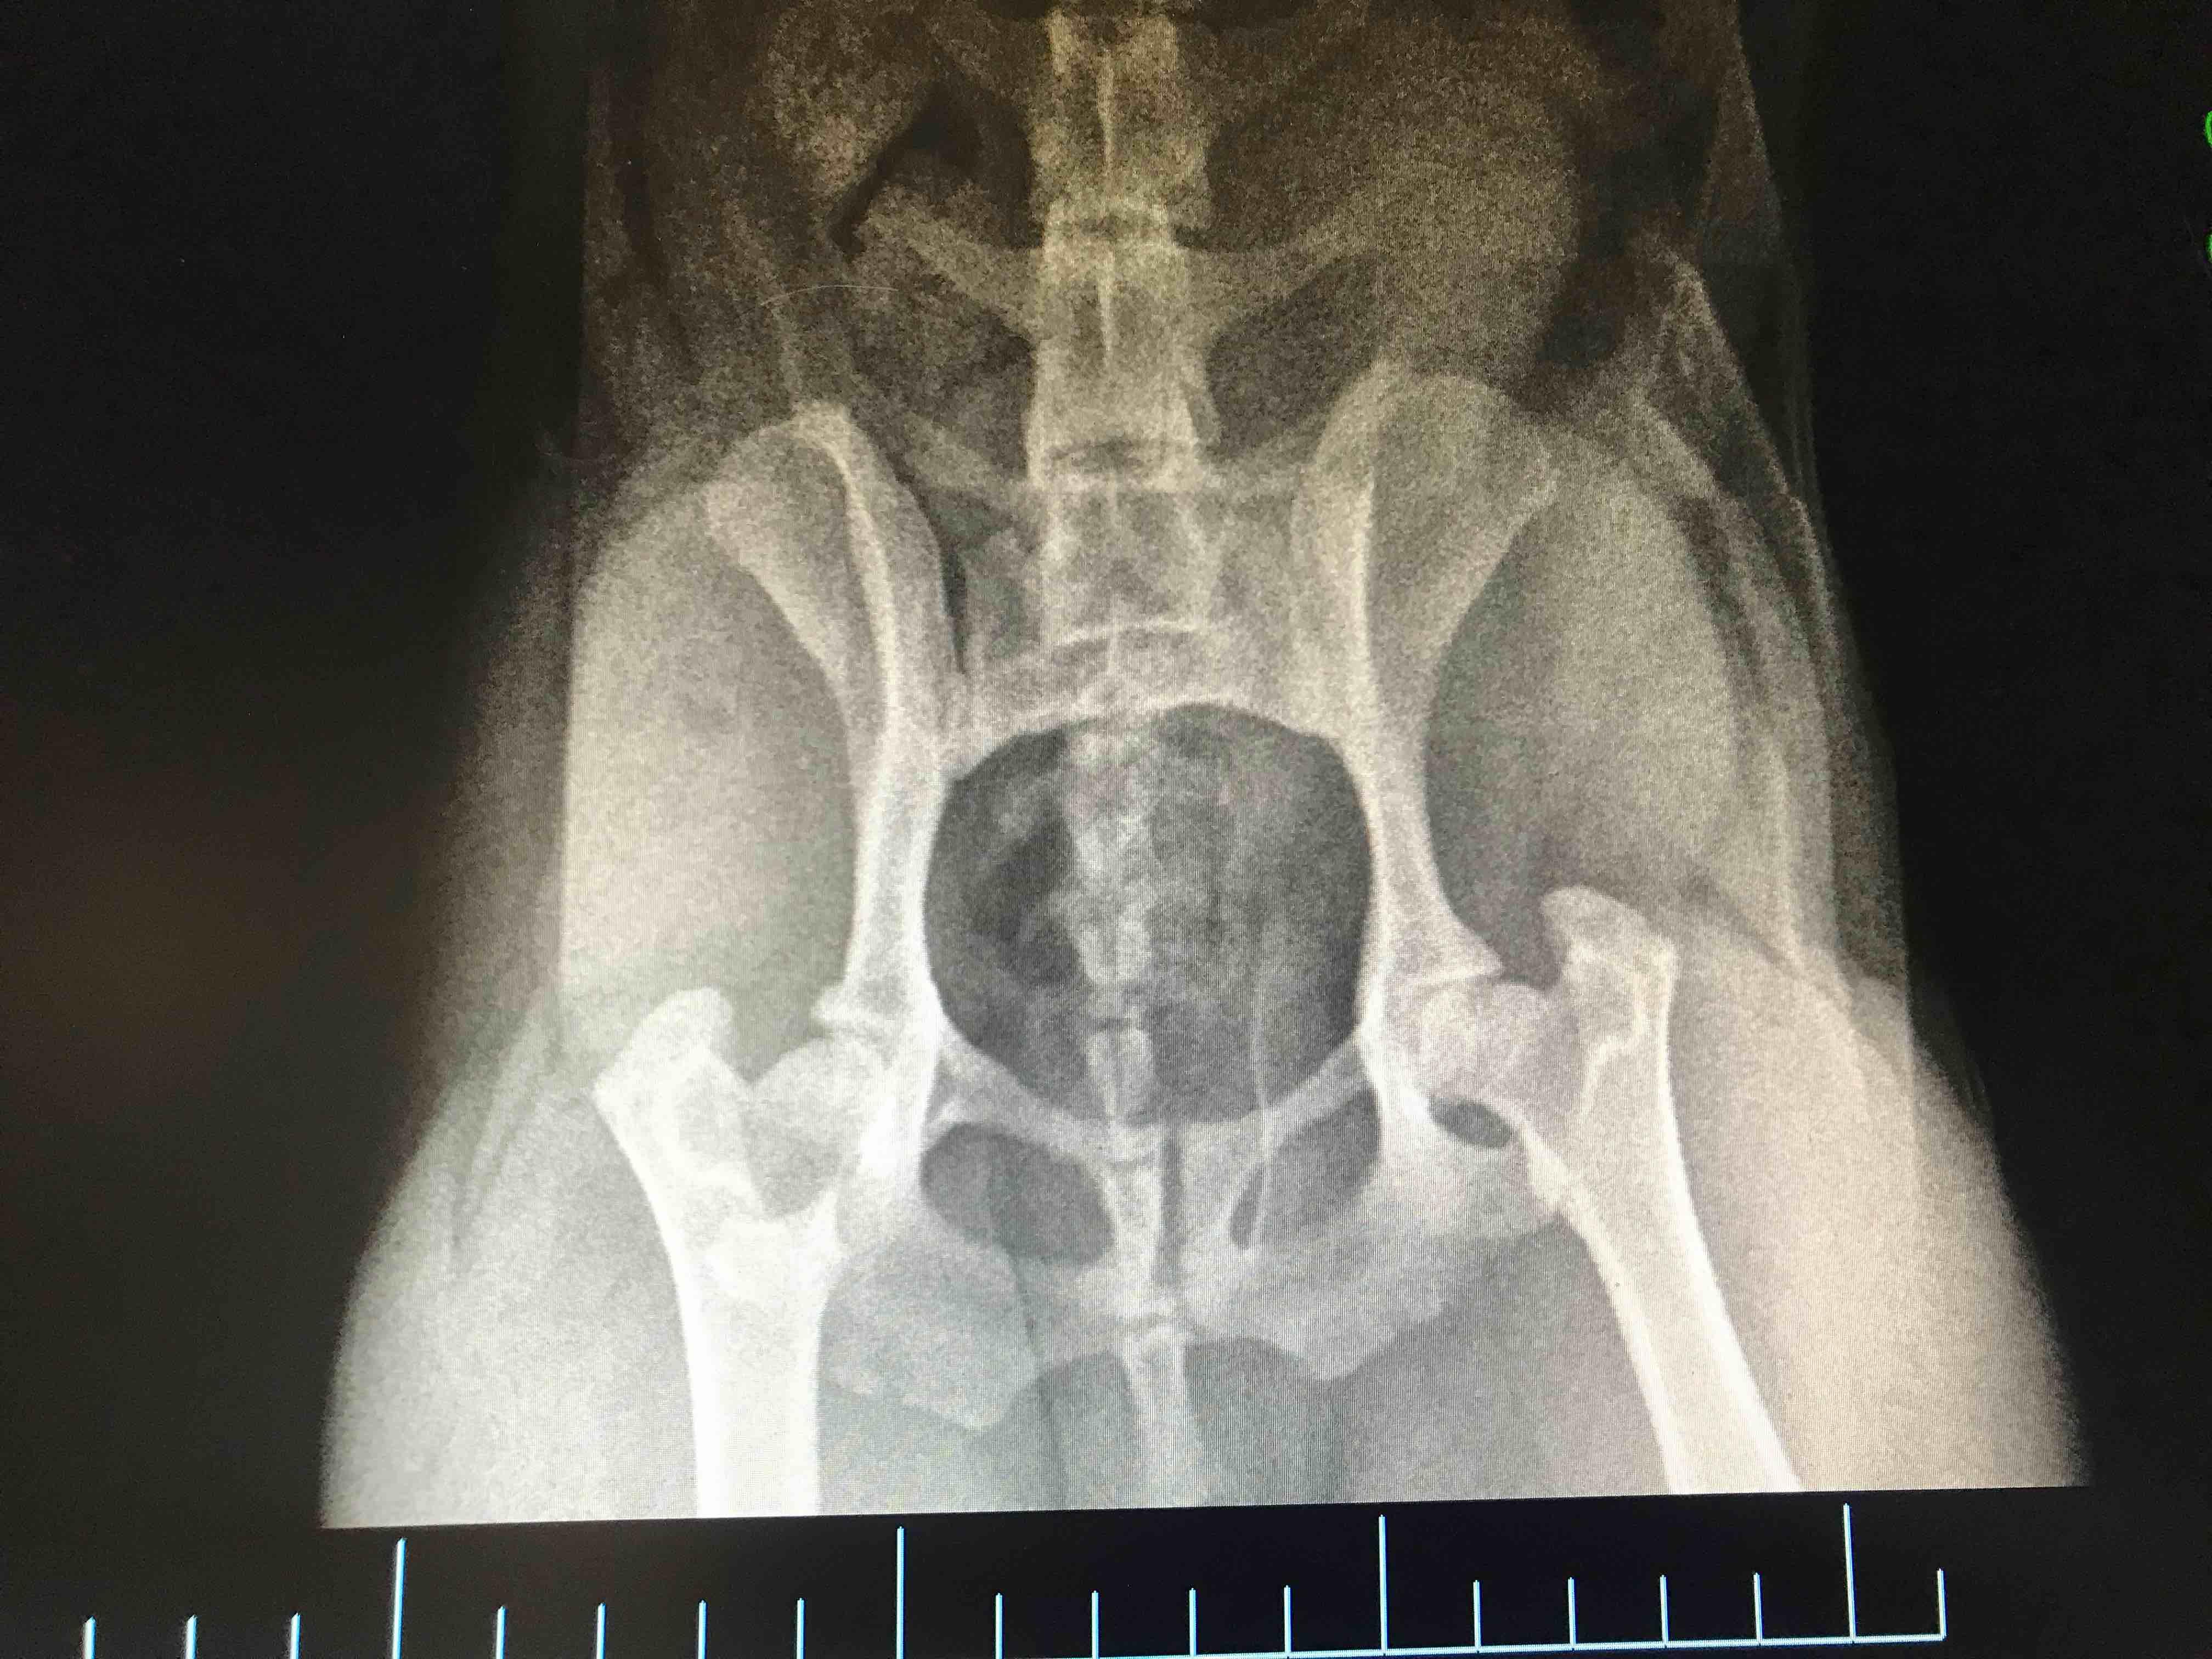

He was diagnosed with avascualar necrosis. Is that the same as Legg-Calvé-Perthes disease? What is it and how will it affect him? Is there any treatment besides surgery? Been giving him glucosamine, hip supplements & taking him swimming but idk if it’s worth it anymore. Doc didn’t have time to go in depth with me. Mom said AC makes his bones & joints hurt more. 1st pic is 5 weeks ago. 2nd is now. Do they look worse?

You are correct those names are used for the same condition. It is typically more common in young, small breed dogs, especially Terrier breeds, but can also occur after trauma. I am assuming your kid has some lameness of the affected limb which is what prompted the vet visits and the xrays. Unfortunately I cannot provide additional comment on the x-rays because it is not legal for us as pet coach experts to diagnose without having examined the pet. But, I hope to provide some information that will be helpful. If the x-rays have not been evaluated by a radiologist this could be very helpful in determining the need for surgery. If this is Legg calve Perthes, in patients that don't respond to medical management within 4 weeks, surgery is typically recommended. For small dogs this typically means removing the head of the upper leg bone (femur, an FHO). For large dogs sometimes a total hip replacement is required. I have attached a link that hopefully will help to explain a little bit about this disease. This is not something your environment caused so it is safe for Boo to stay in AC. I also think the other supportive care that you are providing at home is still a great idea for overall joint health and his other joints. I hope this helps and thank you for using Petcoach! https://www.petcoach.co/article/legg-calve-perthes-disease-in-dogs-avascular-necrosis-of-th/